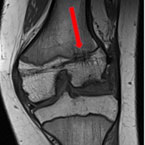

Acquired Distal Femoral Deformity After MPFL Reconstruction

Don’t Do This Case Report

Arianna Trionfo, Alay Shah, Amirhossein Misaghi, Alexandre Arkader